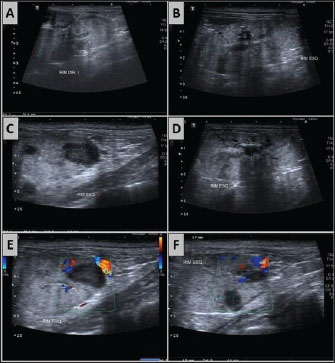

With the administration of meropenem according to the antibiotic susceptibility profile, normalization of the leukogram was observed (Table 1). Renal abscesses, visualized via abdominal ultrasonography (Fig. 2), regressed, leading to urosepsis control. The uremic crisis was resolved. On the 14th day of hospitalization, the patient was discharged for continued treatment at home for the hepatopathy that developed during the infection. The clinical management of CKD was maintained.

Fig. 2. Ultrasound images of the right and left kidneys following treatment with meropenem (8.5 mg/kg SC twice daily for 10 days) in a canine patient with Klebsiella infection. (A–D) Both kidneys show a loss of corticomedullary distinction and definition. (A–C) In the left kidney, there was noticeable remission of the hypoechoic nodular structures, which were previously identified as consistent with renal abscesses.